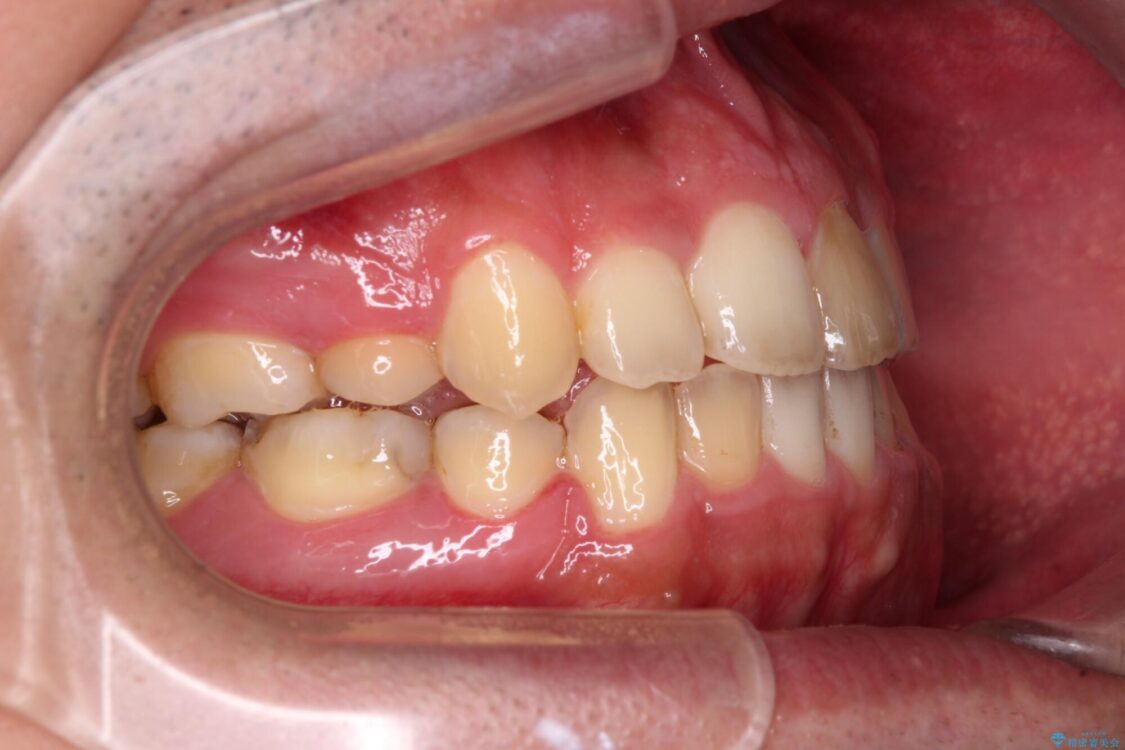

高校時代に行った抜歯矯正が後戻りをしたとのことで来院された患者様です。

治療前

• 後戻りでデコボコの前歯 インビザライン矯正治療 治療前画像